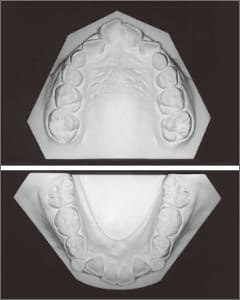

The Class II condition is pronounced, with a significant overjet of 12.5 mm(3). Although the teeth size are large, crowding is relatively mild. The maxillofacial structure has good depth and a robust bone framework(5). The mandible itself is solid , robust gonial angle, but there is significant anterior-posterior displacement relative to the maxilla(ANB 10.0°). While there is no confirmed history of thumb-sucking or similar habits, the lower lip is already pushing up against the maxillary incisors. The cause of this condition is unknown.

The first phase of treatment involved extracting the left and right maxillary deciduous canines. The space created was used to forcibly retract the four anterior teeth, thereby aiming to improve lip closure function (6–9, 11). Morphological changes suggest that lip function differed before and after treatment (6, 9). Subsequently, the first premolars erupted, but extraction is planned to secure space for canine eruption (10). A Class II molar relationship remains, but the significant overjet has improved (11).

In the maxilla, insufficient space for canine eruption was inevitable, necessitating extraction as part of the treatment plan. The maxillary first premolars on both sides were extracted during routine observation to create space for canine eruption (14). Eventually, the canines erupted and settled into relatively favorable positions (15,19,20). In the mandibular dentition, crowding was also present, leading to extraction of the mandibular first premolars on both sides. Treatment with full bracket was then initiated (17).